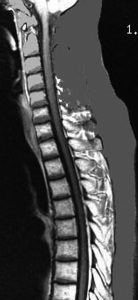

20歳くらいから尿崩症があり,2年後に汎下垂体機能低下症と軽度の認知機能低下を生じました。脳室壁と松果体,神経下垂体にジャーミノーマが広がっているのですが,脊髄背面と脳幹部の周囲にも腫瘍結節が見られました。脳室上衣以外の部位に腫瘍があるので,播種を疑いました。ジャーミノーマの播種というのは実際にはとても珍しくてなかなかみないものです。HCGは軽度の上昇,鼻孔から下垂体部分を生検して病理確定診断して,化学療法と脳脊髄照射 25.2Gy をしました。腫瘍は1コース目の化学療法でほとんど消失したので,他の組織型の悪性混合性胚細胞腫瘍ではないと考えられます。

3年後に脳室壁に再発しました。脳梁と脳弓の機能低下があり認知機能低下は高度でした。松果体と神経下垂体には再発はありません。

脊髄にも再発は見られませんでした。